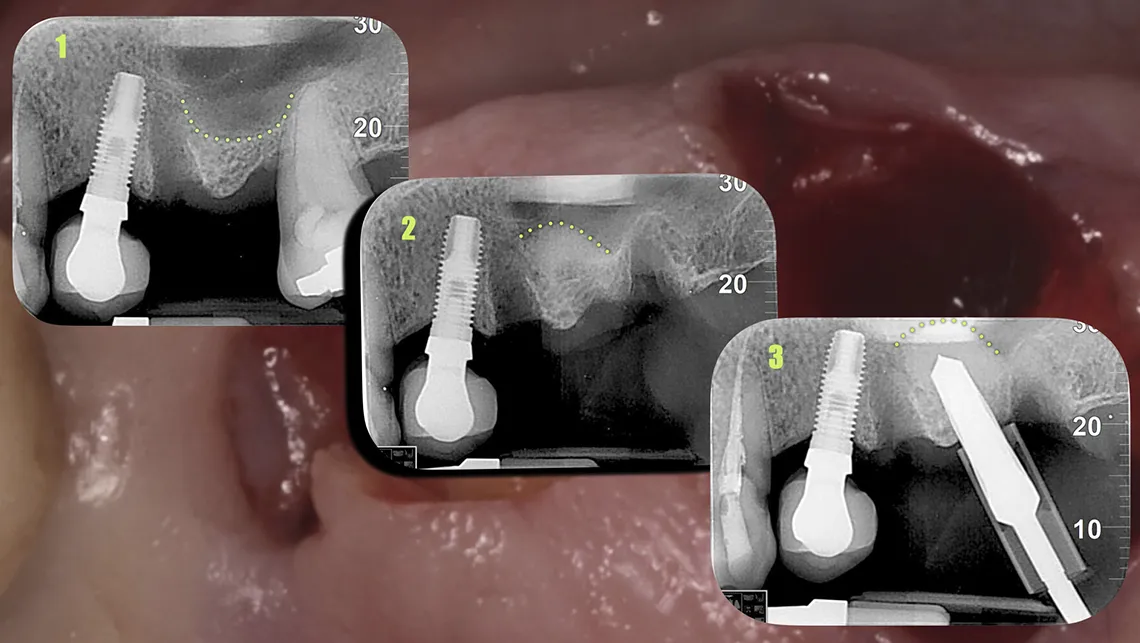

Los estudios disponibles muestran tasas de perforación inferiores al 10% y tasas de éxito cercanas al 97%, incluso en casos con altura ósea residual limitada (figuras 3, 4, 5, 6 y 7).

Fig. 3. Elevación sinusal cerrada. Situación inicial

Fig. 4. Elevación de seno cerrada eficiente. 0,25cc de Biomaterial e implante dental

Fig. 5. Ventana crestal de 4mm de diámetro. Menos es más

Fig. 6. Secuencia de elevación sinusal cerrada. Elevación y compactación del biomaterial

Fig. 7. Elevación sinusal cerrada e implante dental insertado en un solo acto.